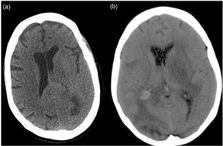

Case Report 1: A 70-year-old woman was seen in an outpatient psychiatric consultation setting after 1 week of mood elevation, sexual disinhibition, and delusional misidentification syndrome. She was being medicated with sertraline and mirtazapine for depression, plus anastrozole for breast cancer relapse prevention. The patient was admitted in our psychiatric hospital for the treatment of a bipolar manic episode. We found cognitive impairment with amnesia, disorientation, dysgraphia, and dyscalculia. Blood work, urine tests, and chest radiography were normal. Electroencephalography was diffusely slow, suggesting encephalic dysfunction. A brain computerized tomography (Figure 1(a)) disclosed left temporal and occipital intra-axial expansive lesions. Admitting psychiatric disorder secondary to breast cancer with brain metastasis, the patient was transferred to a general hospital, but passed away before any neurosurgical procedure was performed.

Figure 1 Brain metastasis leading to bipolar disorder misdiagnosis: (a) left temporal and occipital intra-axial expansive lesions; (b) subcortical left frontal and periventricular right occipital expansive lesions.

Case Report 2: A 40-year-old woman was seen in the emergency room after 1 week of having a depressed mood with delusions of ruin, agitation, and suicidal ideation. In the last 25 years, she had been treated with different types of medication for drug abuse and personality disorder. The patient was admitted in our psychiatric hospital for the treatment of bipolar mixed state. We found ataxia, apathy, and disorganized behavior. Her blood work and urine tests were normal. The chest radiography suggested a 5 cm nodule in the upper lobe of the right lung, highly suggestive of pulmonary neoplasm. Electroencephalography was diffusely slow, suggesting encephalic dysfunction. The computerized tomography brain scan (Figure 1(b)) revealed masses at subcortical left frontal and periventricular right occipital locations. Admitting psychiatric disorder secondary to lung cancer with brain metastasis, the patient was transferred to a general hospital, but passed away before any neurosurgical procedure was performed.